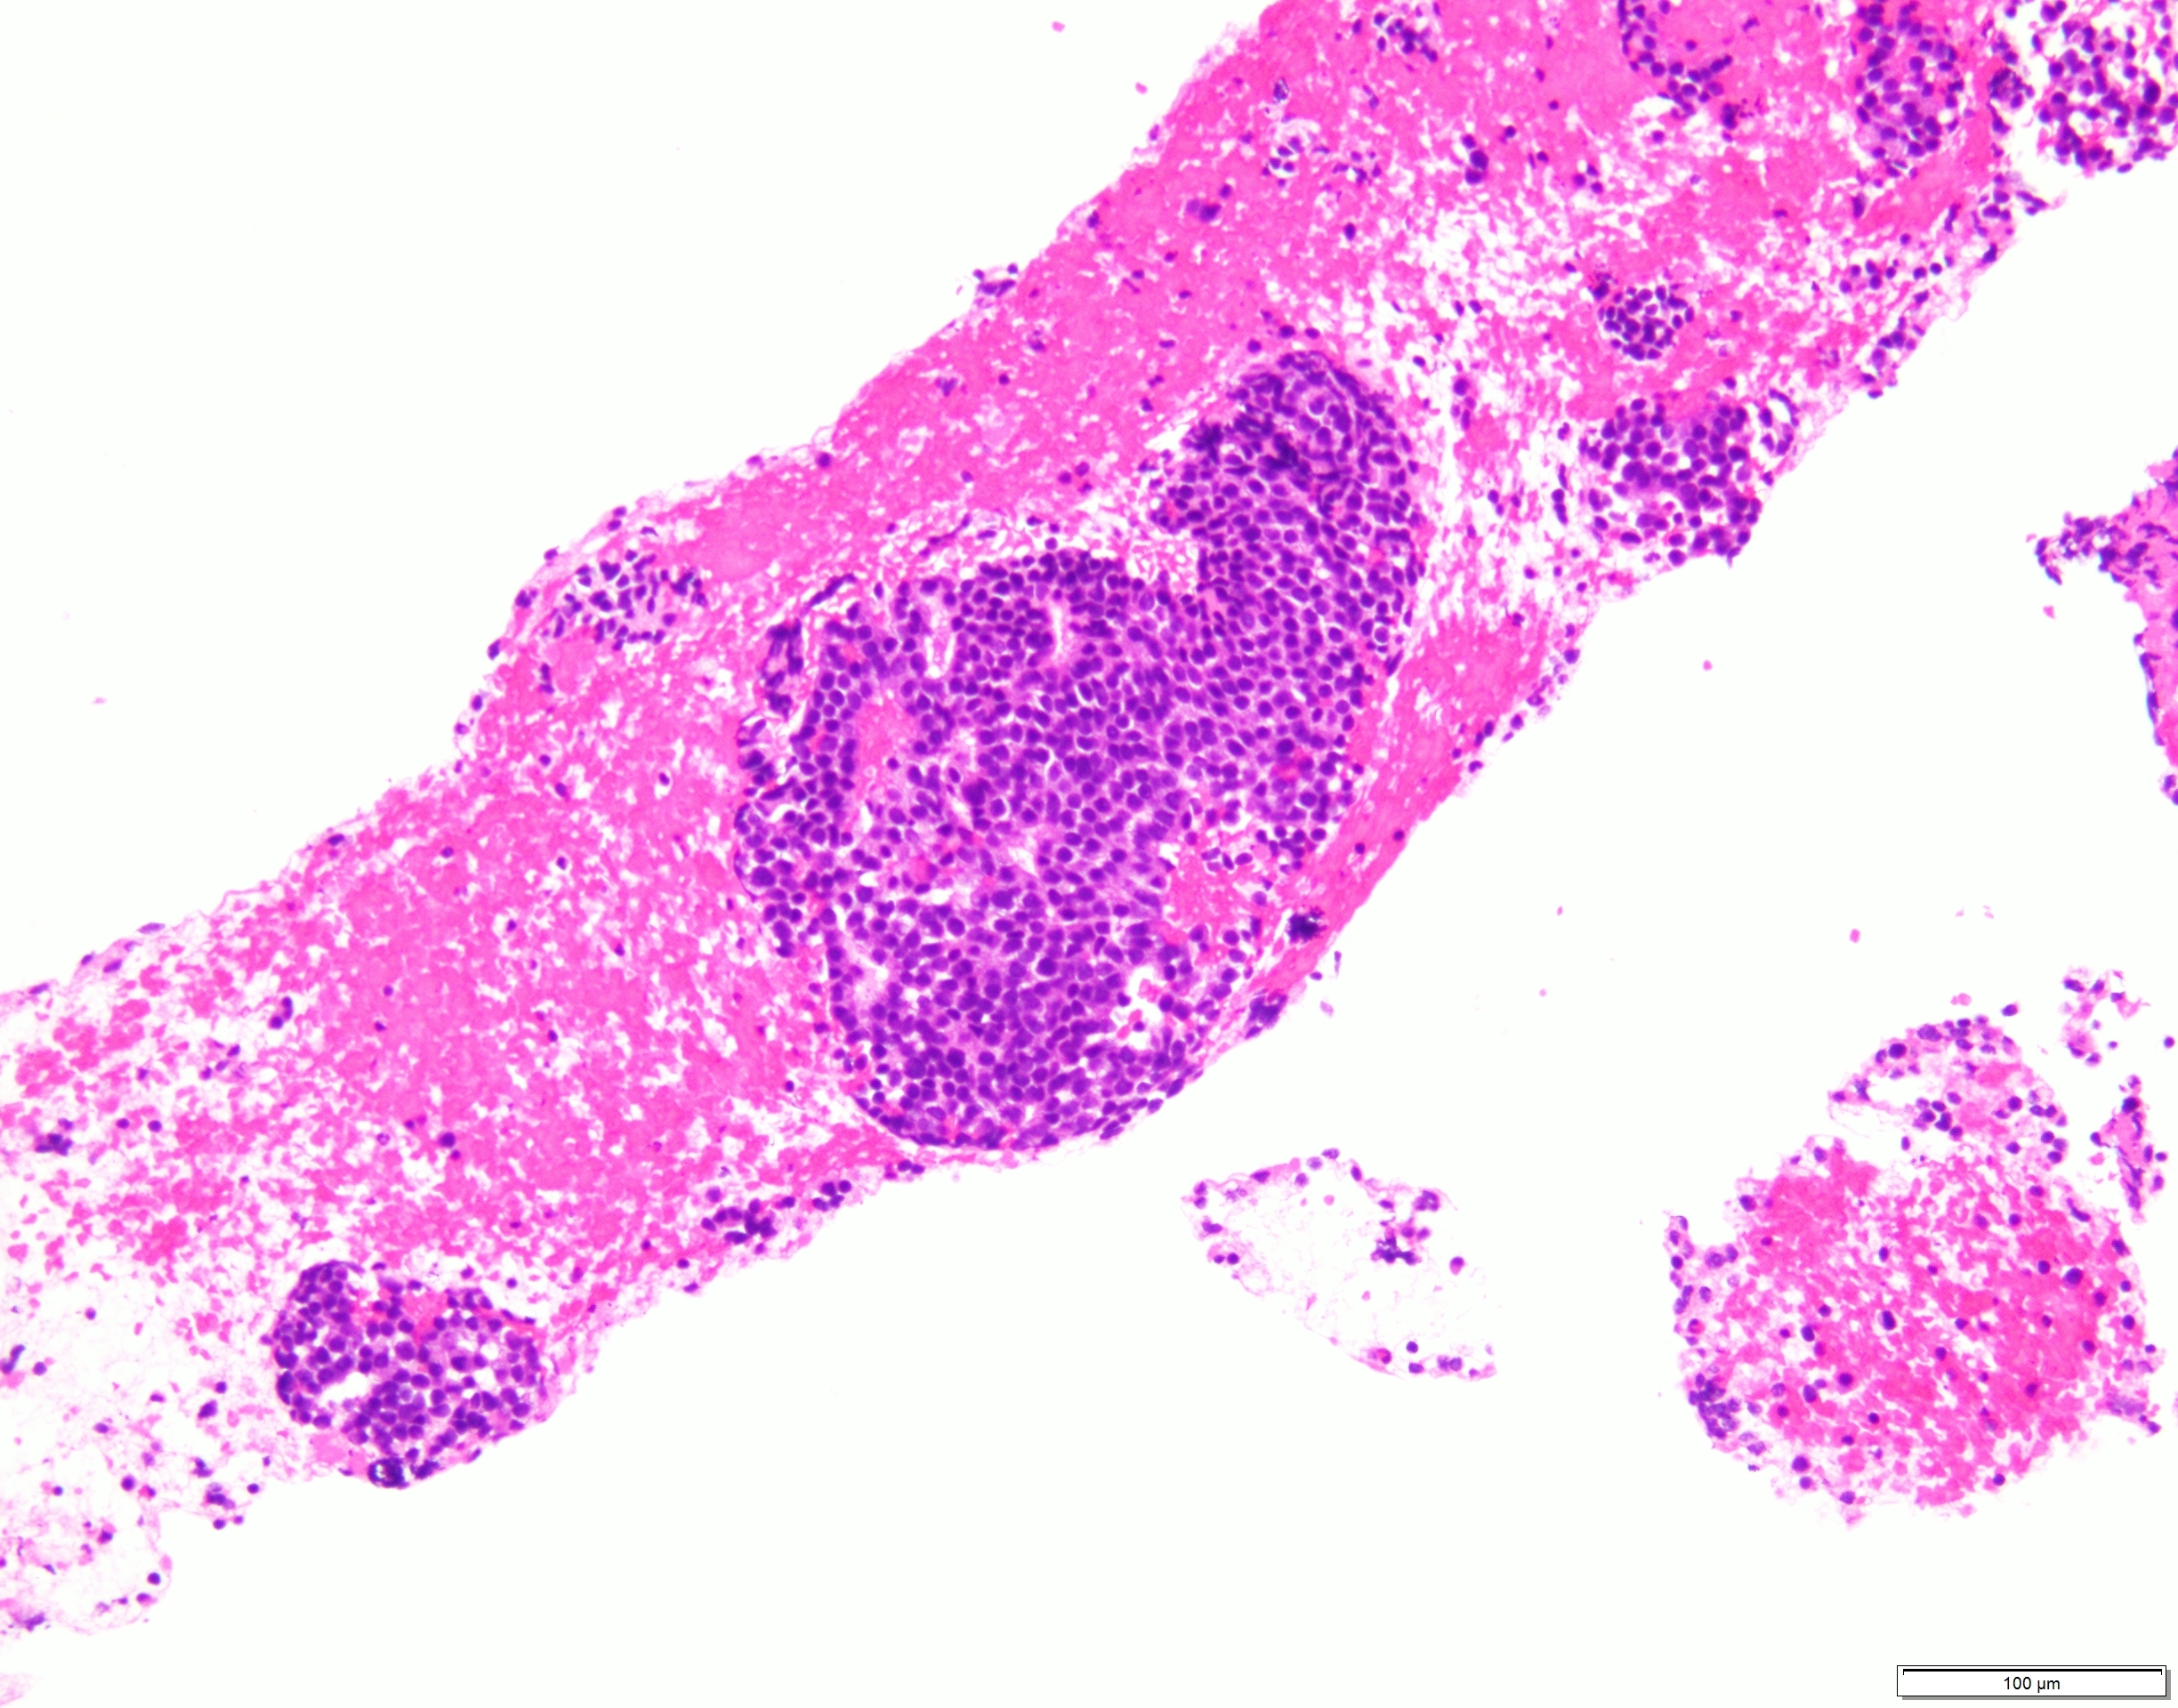

比較的小型で類円形核を有するN/C比の高い細胞が集簇性〜孤立性に多数認められた。

出現している異型細胞は一様で核線の形成やロゼット様の構造を認め、NETを推定した。

異型細胞が血管間質を伴うように出現する箇所も見られ、細胞の形態からもSPNとの鑑別を要する細胞像であるとの意見もあった。

組織でも同様の異型細胞を認め、クロモグラニン陽性、MIB-1 LI 15%、ER陰性、GATA3陰性を呈し、NET G2と診断された。

HE×10 HE×20 HE×40 クロモグラニン×40